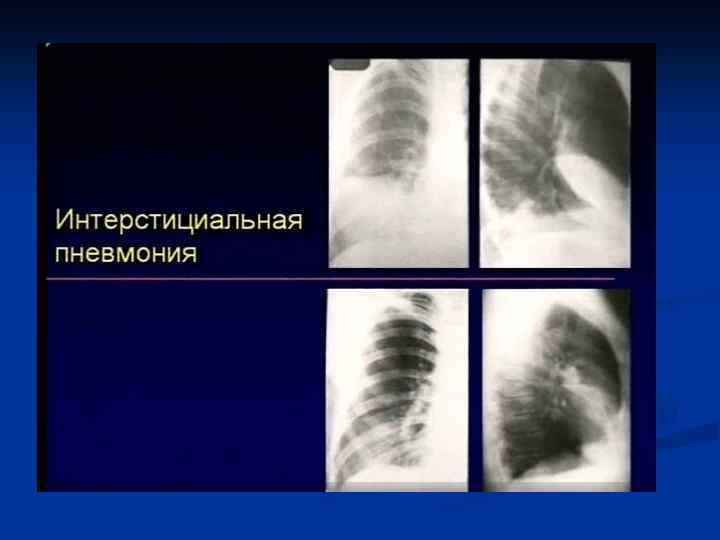

Интерстициальная пневмония

Интерстициальная пневмония n n n n Хуже диагностируются чем паренхиматозные Чаще – постгриппозные Вяло текут ОАК – почти норма Субфебрилитет Жалобы на недомогание, сухой кашель, вялость Это продуктивное воспаление (лечится тяжело)

Интерстициальная пневмония n n Характеризуется воспалительной инфильтрацией интерстиция Вызывающие ее микроорганизмы: вирусы, микоплазма, рикетсии, приводят к отеку и лимфацитарной инфильтрации стенок бронхов, Далее распространяется по междольковым перегородкам. Лимфоцитарная инфильтрация перибронхиальных альвеол, что придает сходство с очаговой ПН

Интерстициальная ПН - ретикулярные = сетчатые изменения легочного рисунка - преимущественно центральным = прикорневым распределением - могут быть очаговые сливающиеся уплотнения легочной ткани